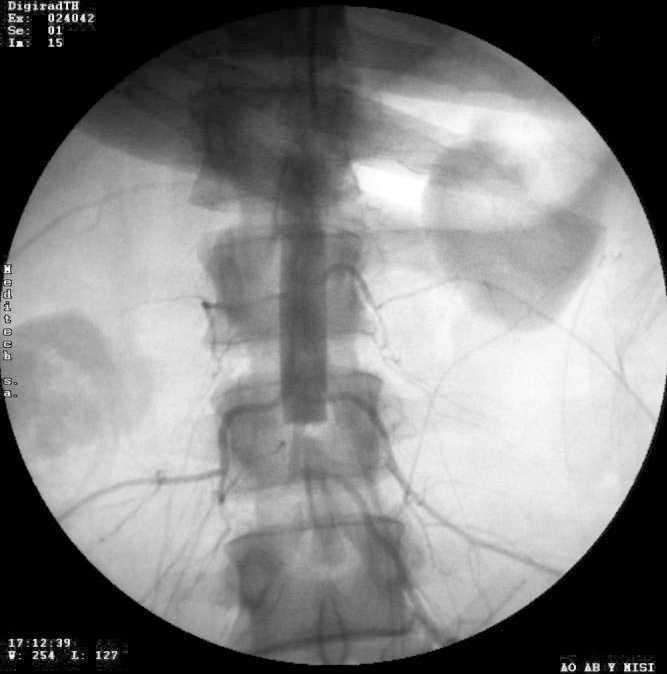

Los estudios radiológicos solicitados evidenciaban fractura por estallido de cabeza de húmero derecho, fractura del tercio medio de la diáfisis humeral derecha, fractura de diáfisis media del fémur derecho y neumotórax izquierdo grado I, que fue drenado. Se realizó resonancia magnética nuclear de columna lumbosacra que descartó lesiones medulares, hallándose como única lesión una fractura del sacro. Tras la reanimación inicial se realizó tomografía abdominal con contraste endovenoso en la que se descartaron lesiones de órganos sólidos. No se visualizaron anormalidades a nivel aórtico, pero debido a la semiología se realizó angiografía de aorta abdominal y miembros inferiores (fig. 1), que demostró oclusión aórtica a nivel infrarrenal sin circulación distal.

Figura 1. Aortograma abdominal que evidencia stop infrarrenal del flujo a nivel de la vértebra lumbar 3.